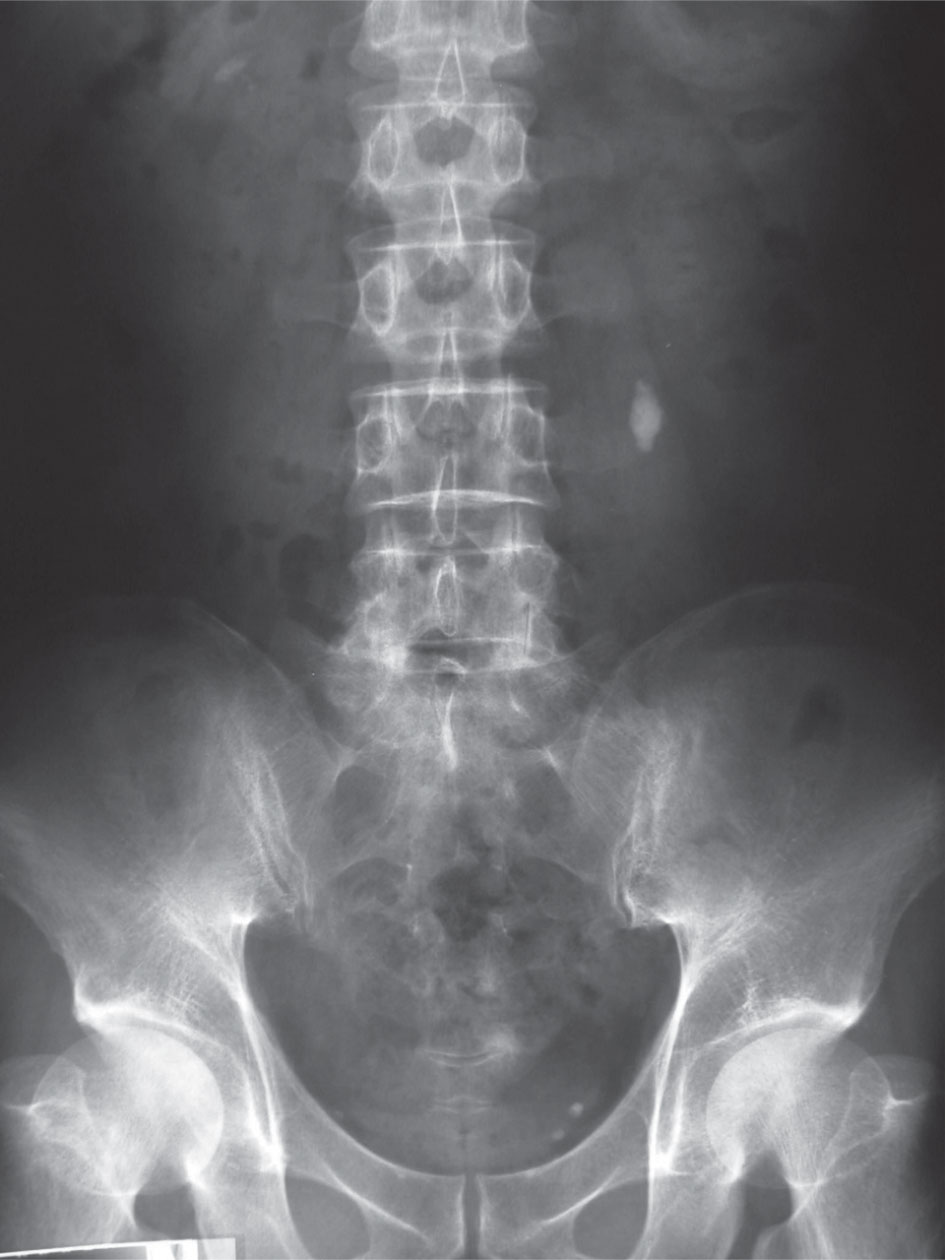

شعاعياً: التشخيص الشعاعي ضروري في مثل هذه الحالات، وهناك عدة صفات مميزة لهذه الحالة وهي:

> صورة البطن البسيطة: المنظر الشعاعي النموذجي للحصيات المرافقة لفرط نشاط مجاورات الدرق هو التكلس المتعدد الذي يصيب إما كلية واحدة وإما أن يكون ثنائي الجانب في الكثير من الحالات ويعرف باسم الكلاس الكلوي nephrocalcinosis.

الاستقصاءات الشعاعية: تظهر صورة البطن البسيطة وجود تكلسات كلوية في منطقة اللب الكلوي nephrocalcinosis in the renal medulla، كما قد تظهر علامات تخلخل عظمي في الحالات المتأخرة.